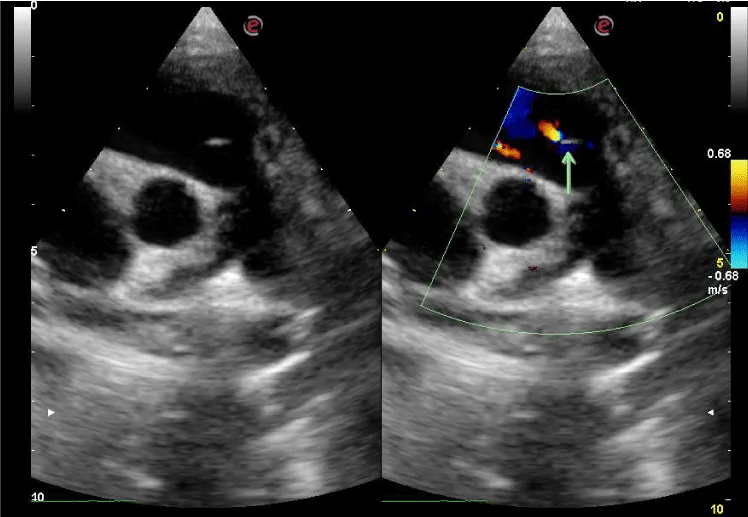

Doppler windows were the parasternal long-axis, parasternal short-axis, and apical five-chamber views for the aortic valve (Figure 1); and the parasternal long-axis, parasternal short-axis, and apical four-chamber views for the mitral valve. For the tricuspid valve, the right ventricular inflow view and parasternal and apical four and five chamber views were used (Figure 2) while the right ventricular outflow tract and the high parasternal short-axis view was used for the pulmonary valve (Figure 3). The flow signal was adjudged as regurgitant when it was observed as a reversed flow away from the valve by color Doppler echocardiography and when it lasted more than 100 msec by M-mode color flow mapping [6,12].